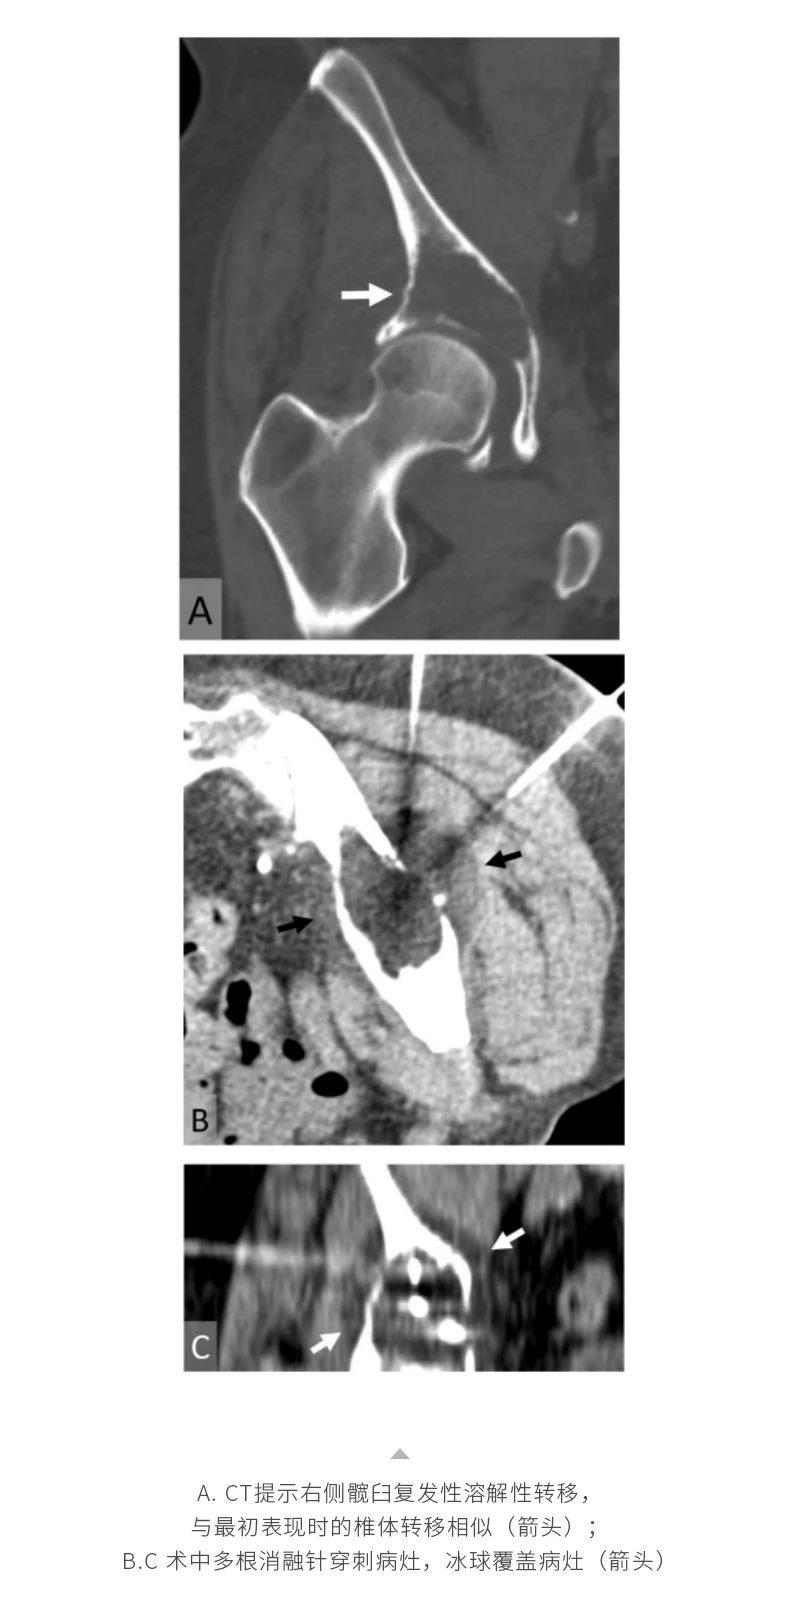

冷凍消融骨腫瘤——【海杰亞科研資訊】第285期